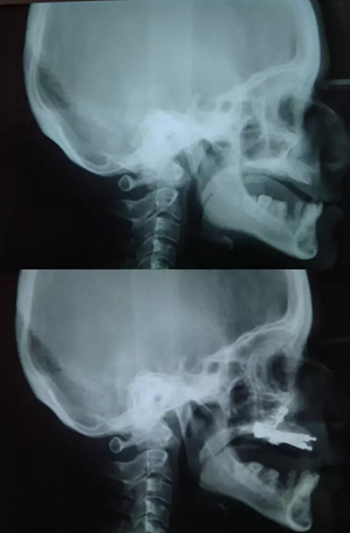

圖 3. 側(cè)位片(術(shù)前及牽張前)

該患者的治療目標(biāo)是恢復(fù)牙頜面的正常功能和美觀,包括頜骨的垂直關(guān)系及咬合關(guān)系。治療步驟分別是術(shù)前診斷,制備引導(dǎo)性義齒,外科手術(shù)(Le FortⅠ型截骨牽張成骨),種植體植入及最終的義齒修復(fù)。上頜牽張 10 天(每天 0.5 mm×2 次),二期拆除牽張器并行種植體植入,術(shù)后出現(xiàn)輕微的感覺異常及開口困難,癥狀于 2 周后緩解。經(jīng)頭影測量可見 A 點(diǎn)、ANS 點(diǎn)、上唇、鼻尖點(diǎn)分別前移 6 mm、 8 mm、5 mm、2 mm。最后行義齒修復(fù)上頜牙列缺失?;颊邔?duì)最終的美觀及功能恢復(fù)感到滿意。